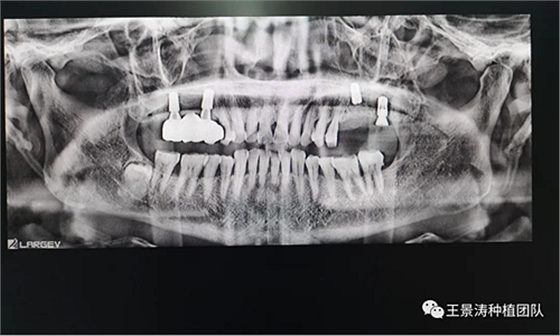

左側(cè)下頜第二磨牙及右側(cè)下頜第一磨牙同時(shí)即刻種植病例?;颊吣贻p女性,無系統(tǒng)性疾病。37及46殘冠及殘根,且46劈裂,無法冠修復(fù),必須拔除。37根尖慢性炎癥,大量肉芽組織存在,46根分叉較高,根分叉骨質(zhì)尚可。CBCT示:根尖骨質(zhì)至下牙槽神經(jīng)管距離可滿足種植體的初期穩(wěn)定性,遂考慮即刻種植,并在種植體周邊填入骨粉并覆蓋骨膜,雙側(cè)的種植體初期穩(wěn)定性相差無幾,但考慮到37根尖慢性炎癥較大,遂給予埋入式種植。